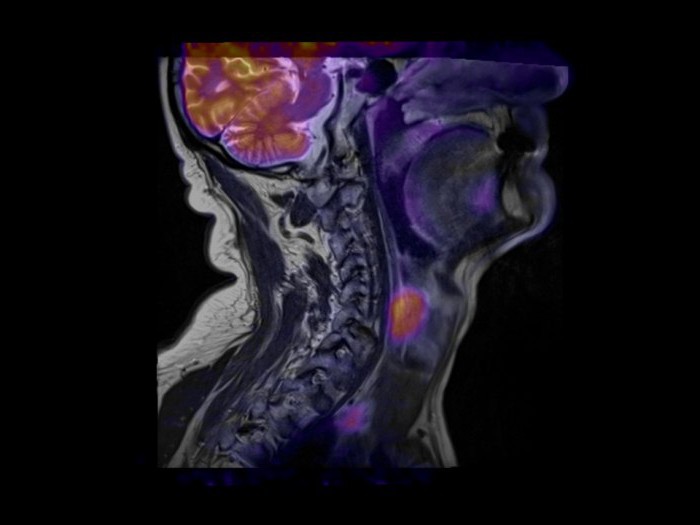

МРТ мягких тканей помогает врачу, например, выяснить причину компрессии нерва или сосуда. Довольно часто проводится МРТ мягких тканей шеи – для определения патологий глотки, гортани, а также щитовидной железы.

Магниторезонансная томография мягких тканей шеи присутствие нарушений после травм, локализацию очагов инфекций, масштабы изменений, вызванных болезнью. Томография позволяет выявлять раковые новообразования на коже, подкожных слоях, сухожилиях. До распространения томографии причины боли в ногах сложно определялись. Сейчас

Магнитно-резонансная томография шейного отдела позвоночника | 2 500р. |

Магнитно-резонансная томография краниовертебрального перехода и шейного отдела позвоночника | 2 700р. |